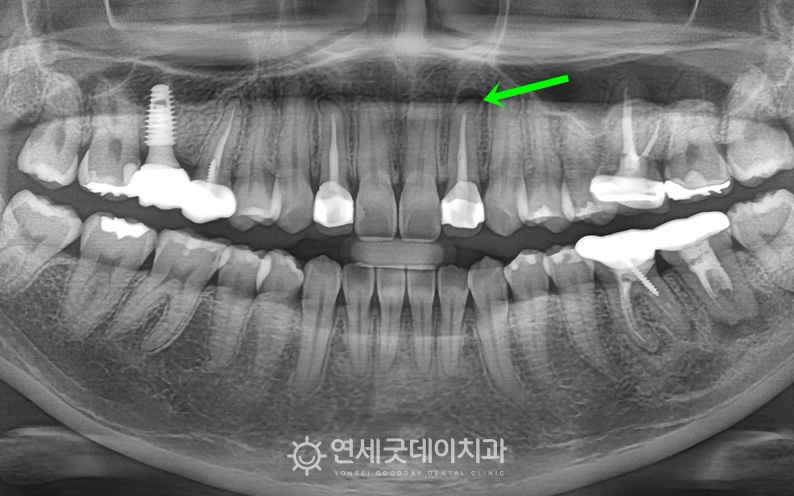

재신경차료 전 치근단에 염증이 관찰되는 모습

▲ 치료 전 엑스레이 (촬영시기 : 2025년 8월)

타원에서 10년 전에 크라운 치료를 받았던 부위에

뿌리 끝 염증 즉, 치근단 병소가 관찰됩니다.

신경관 내 문제를 일으켰던 세균이

완벽히 제거되지 못하면서

다시 염증을 유발하며 치아 뿌리 주변의 뼈를 녹이고 있었습니다.